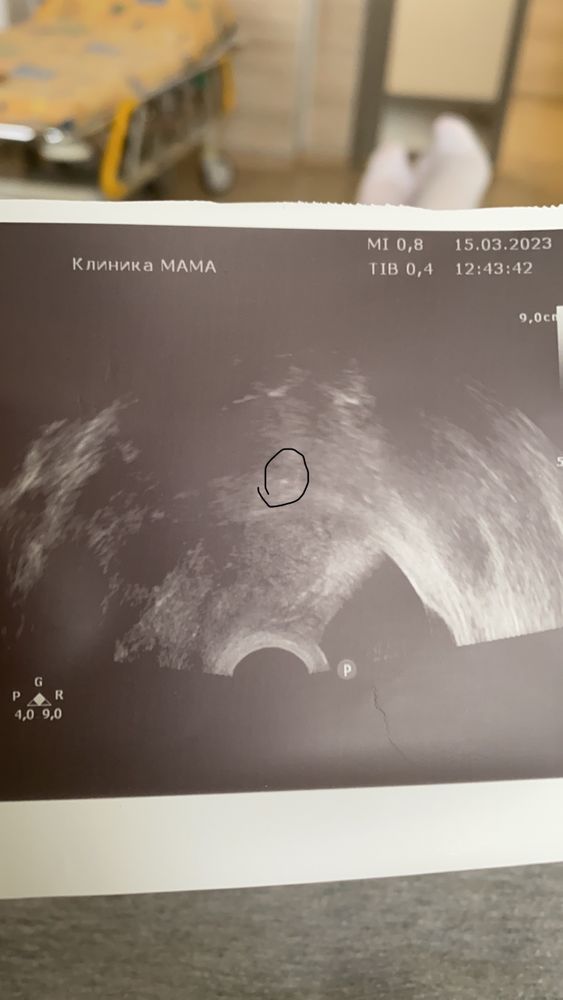

Поздравляю! А Вам проверяли наличие эмбриона вагинальным датчиком? И да, на картинке не сам эмбрион, а пузырек со средой, в которой он жил до подсадки. Мне на переносе врач так объяснял. Правда, я еще видела и сам эмбрион на большом экране. Чуть не прослезилась, вроде по 4АВ был, а на переносе уже было видно, как он почти наполовину из оболочки вылез. Стремился развиваться УДачи Вам! И заветных //

Irina, мне на узи показали пятнышко это и все,сказали вот ваш ребёнок.больше ни чего спасибо большое